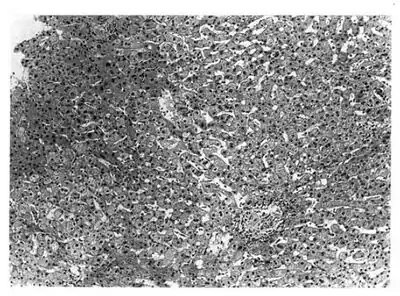

| Image of the liver showed a focus of granuloma in lobule | |

Idiopathic granulomatous hepatitis is a rare medical condition characterised by granulomas in the liver, recurrent fever, myalgia, and fatigue. The condition is not a true hepatitis, and some experts believe it is a variant of sarcoidosis.[1][2]